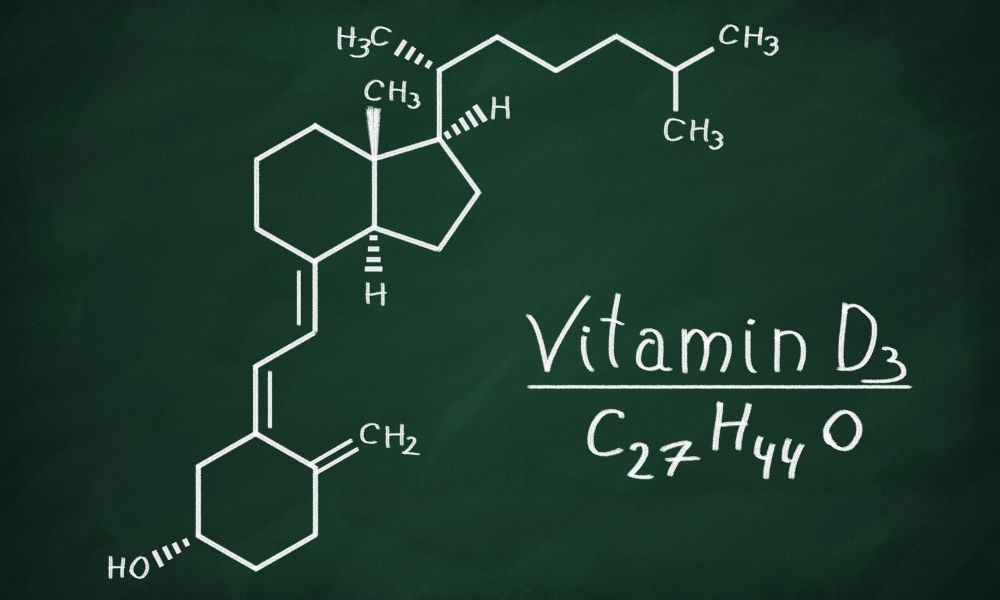

Czym jest witamina D3?

Definicja i rola w organizmie

Witamina D3, znana również jako cholekalcyferol, jest kluczowym składnikiem odżywczym, który odgrywa fundamentalną rolę w prawidłowym funkcjonowaniu naszego organizmu. Jest to związek rozpuszczalny w tłuszczach, który w rzeczywistości działa jak hormon, wpływając na wiele procesów biologicznych.

Różnica między witaminą D2 a D3

Witamina D występuje w dwóch głównych formach: D2 (ergokalcyferol) i D3 (cholekalcyferol). Choć obie formy są wykorzystywane w suplementach, istnieją między nimi istotne różnice:

Witamina D3 jest również efektywniej przekształcana w organizm w aktywną formę witaminy D, zwaną kalcytriolem. Kalcytriol jest hormonem steroidowym, który reguluje ekspresję genów w wielu tkankach organizmu, wpływając na metabolizm, wzrost i różnicowanie komórek.